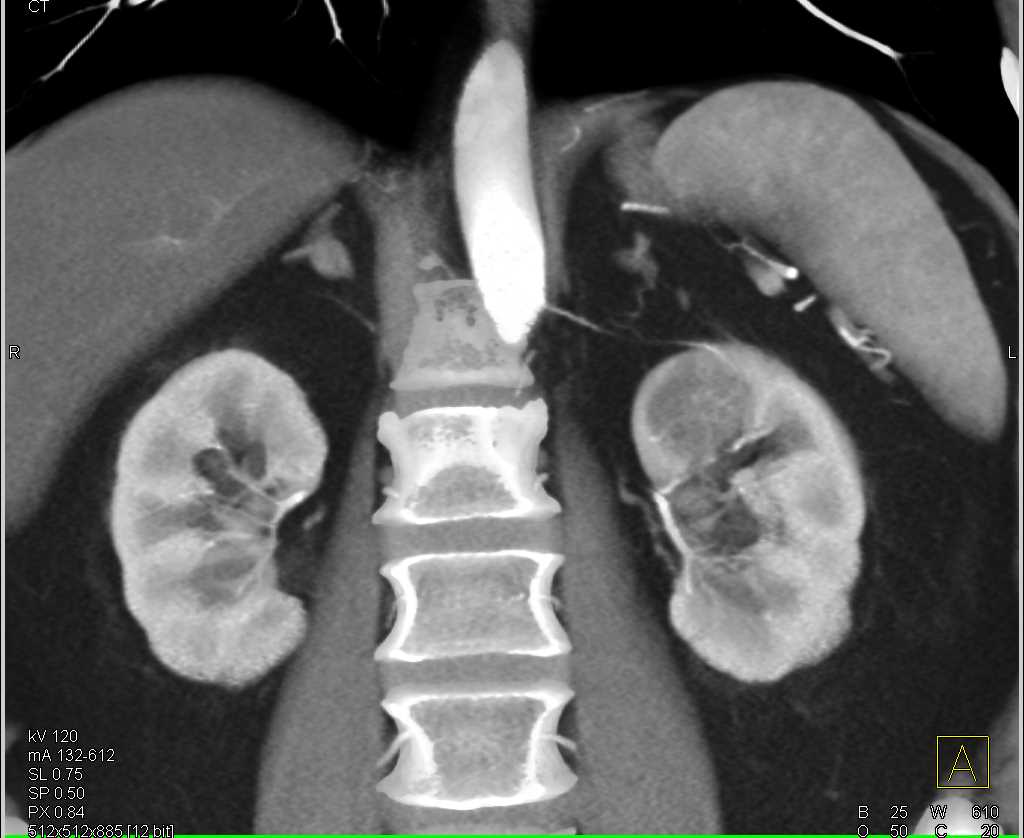

Left Nephrectomy with Contralateral Adrenal Metastases